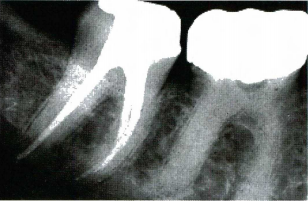

2.嚴重的根管解剖變異 牙根重度彎曲、根管重度鈣化和根管分叉等解剖因素使根管治療器械和充填材料無法到達根管工作長度(根尖止點)。

1673147708712.png